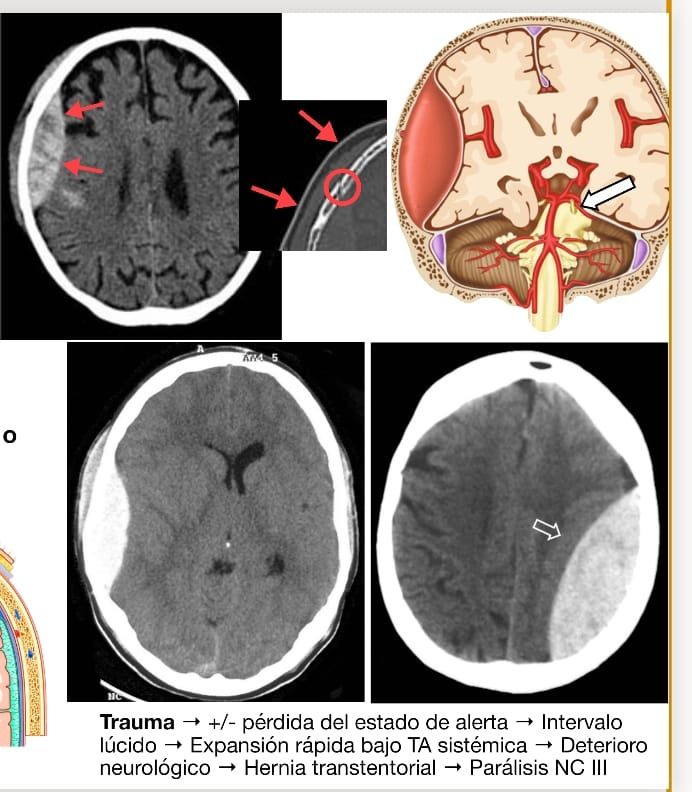

Las figuras 1, 2 y 3 ilustran ejemplos de signo, hallazgo y patrón.

Signos indicadores de patología. Son los más abundantes. Pueden sugerir un diagnóstico específico o un listado breve de diagnóstico diferencial. Pertenecen a este grupo, por mencionar alguno, el signo del sombrero de Napoleón invertido (en la espondilólisis con espondilolistesis), el signo del camalote (en el quiste hidatídico roto), el signo de la omega (en la enfermedad de Crohn) o el signo de la cabeza de medusa (en el angioma cerebral).